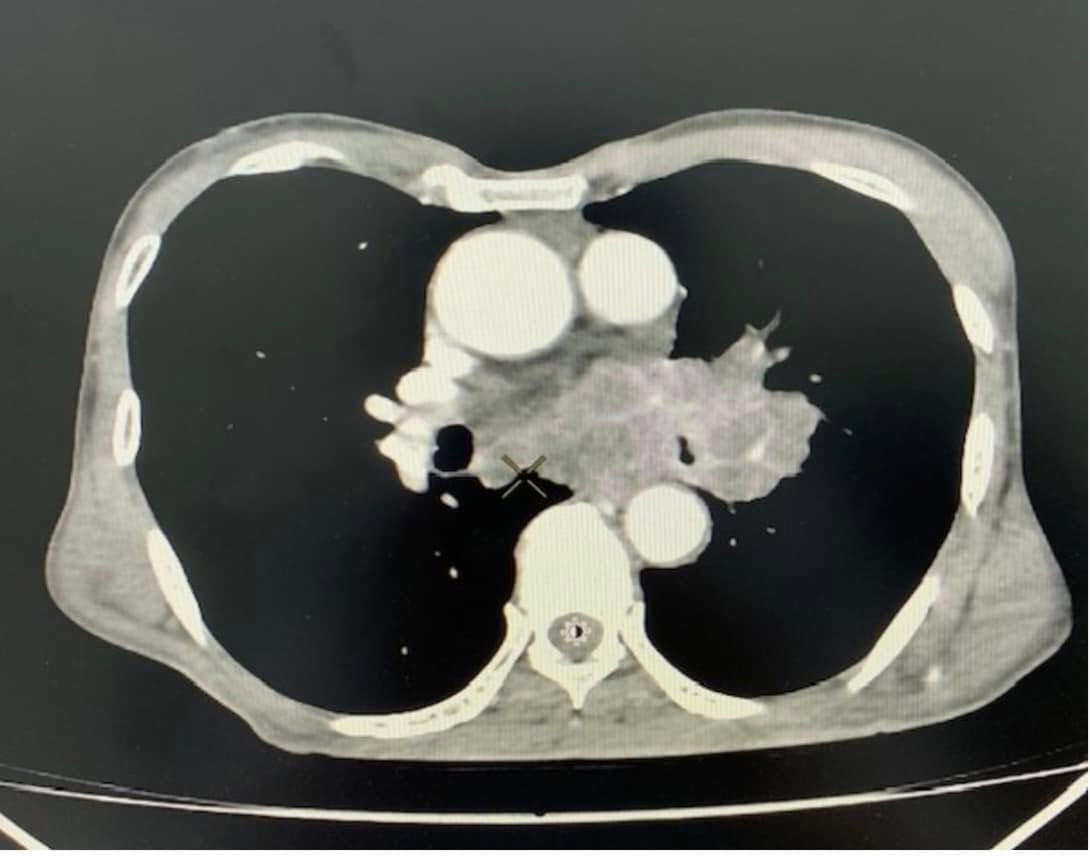

18/12/2024 21:20Người đàn ông phát hiện khối u ác tính từ dấu hiệu đơn giản

Ông T.V.N. (69 tuổi, trú tại Hà Nội) cảm thấy mệt mỏi, giảm cân nên đến khám tại Bệnh viện Bệnh Nhiệt đới Trung ương (Hà Nội).

Kết quả chụp cắt lớp vi tính lồng ngực cho thấy bệnh nhân có khối u vùng trung thất và rốn phổi trái, bờ không đều, ngấm thuốc ở thành khối và vào các vách bên trong. Tổn thương hướng tới u phổi, dạng u phế quản trung tâm, xâm lấn trung thất, gây hẹp phế quản gốc trái. Sau khi có kết quả, ông N. đã được chuyển đến bệnh viện chuyên khoa để điều trị tiếp.